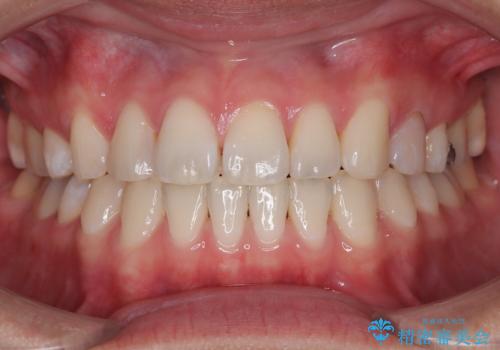

50代女性 八重歯を矯正治療 歯並びの中等度のがたつき